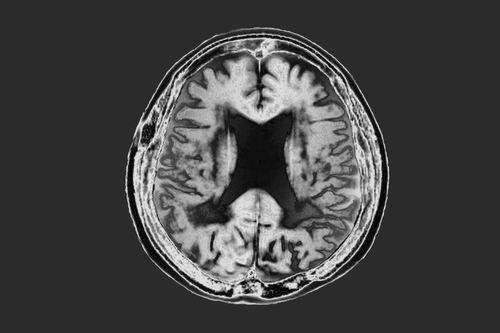

由于家中有两位相同疾病的患者,赵女士有些担忧。近期,她觉得自己主观认知下降、记忆力减退得厉害,以致经常独自流泪,情绪不高。了解情况后,吴婷一边安抚赵女士情绪,一边为其安排了头部核磁共振、心理健康测试以及高危基因筛查等项目。尽管核磁共振结果和心理健康测量均正常,但是赵女士在阿尔茨海默病相关的ApoE基因检测中显示为中高度危险型。因此,吴婷建议赵女士接受自己是高危人群的现实,并接受相应的药物治疗、康复治疗以及改善生活方式等早期综合治疗。在吴婷的帮助下,赵女士渐渐不再焦虑,和家人一起重新规划生活,定期复查,做好日常治疗,以延缓疾病发展。